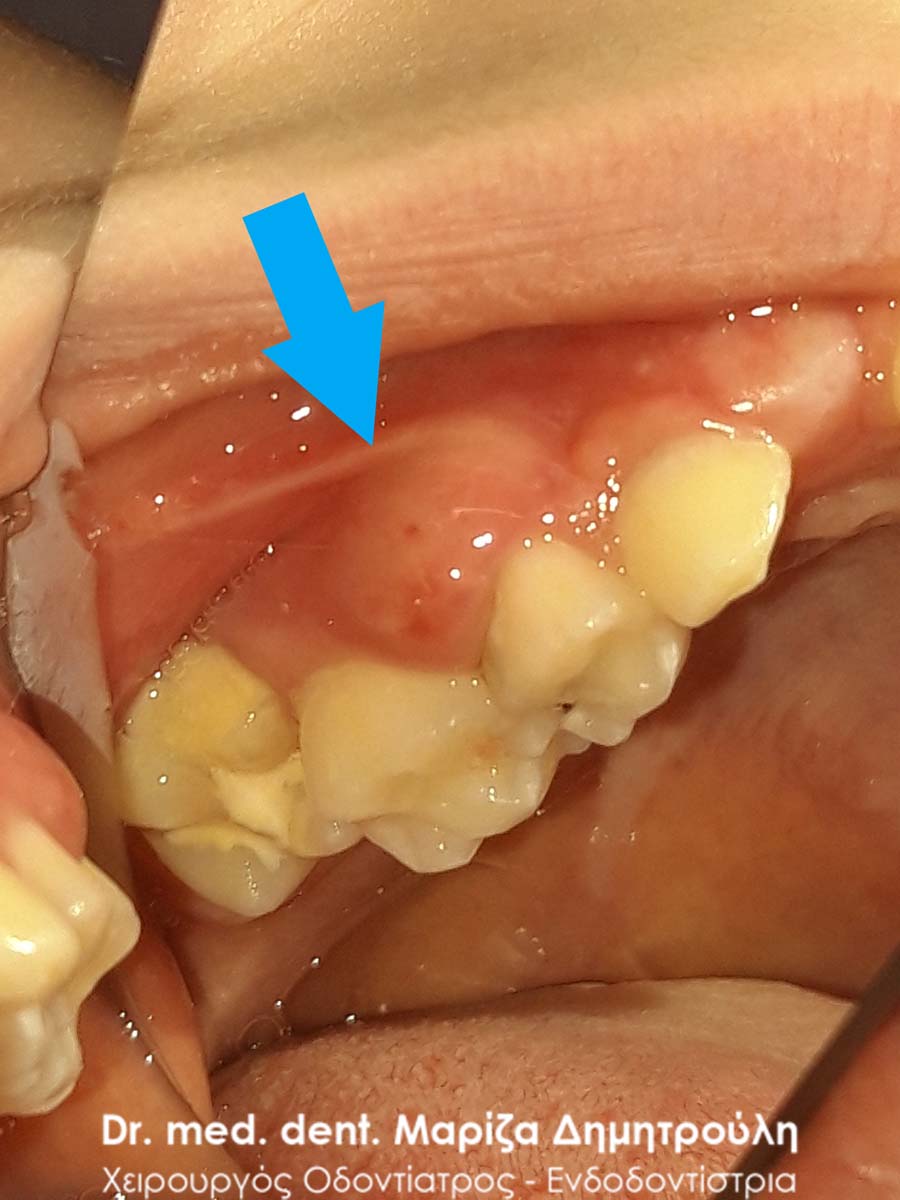

Περιστατικό – Νεκρό παιδικό δόντι με επέκταση του ούλου μέσα στο δόντι

Στο αγόρι αυτό το δόντι του είχε παραμείνει  αθεράπευτο για μεγάλο χρονικό διάστημα. Αποτέλεσμα ήταν η νέκρωση του παιδικού δοντιού και η επέκταση του ούλου μέσα στην τερηδονική κοιλότητα του δοντιού. Το παιδί φυσικά δεν πονά , εφόσον το δόντι έχει νεκρωθεί. Η λύση θεραπείας ήταν η άμεση εξαγωγή του δοντιού, εφόσον δεν είναι καθόλου καλό ένα δόντι με φλεγμονή να παραμένει στο στόμα ενός παιδιού.